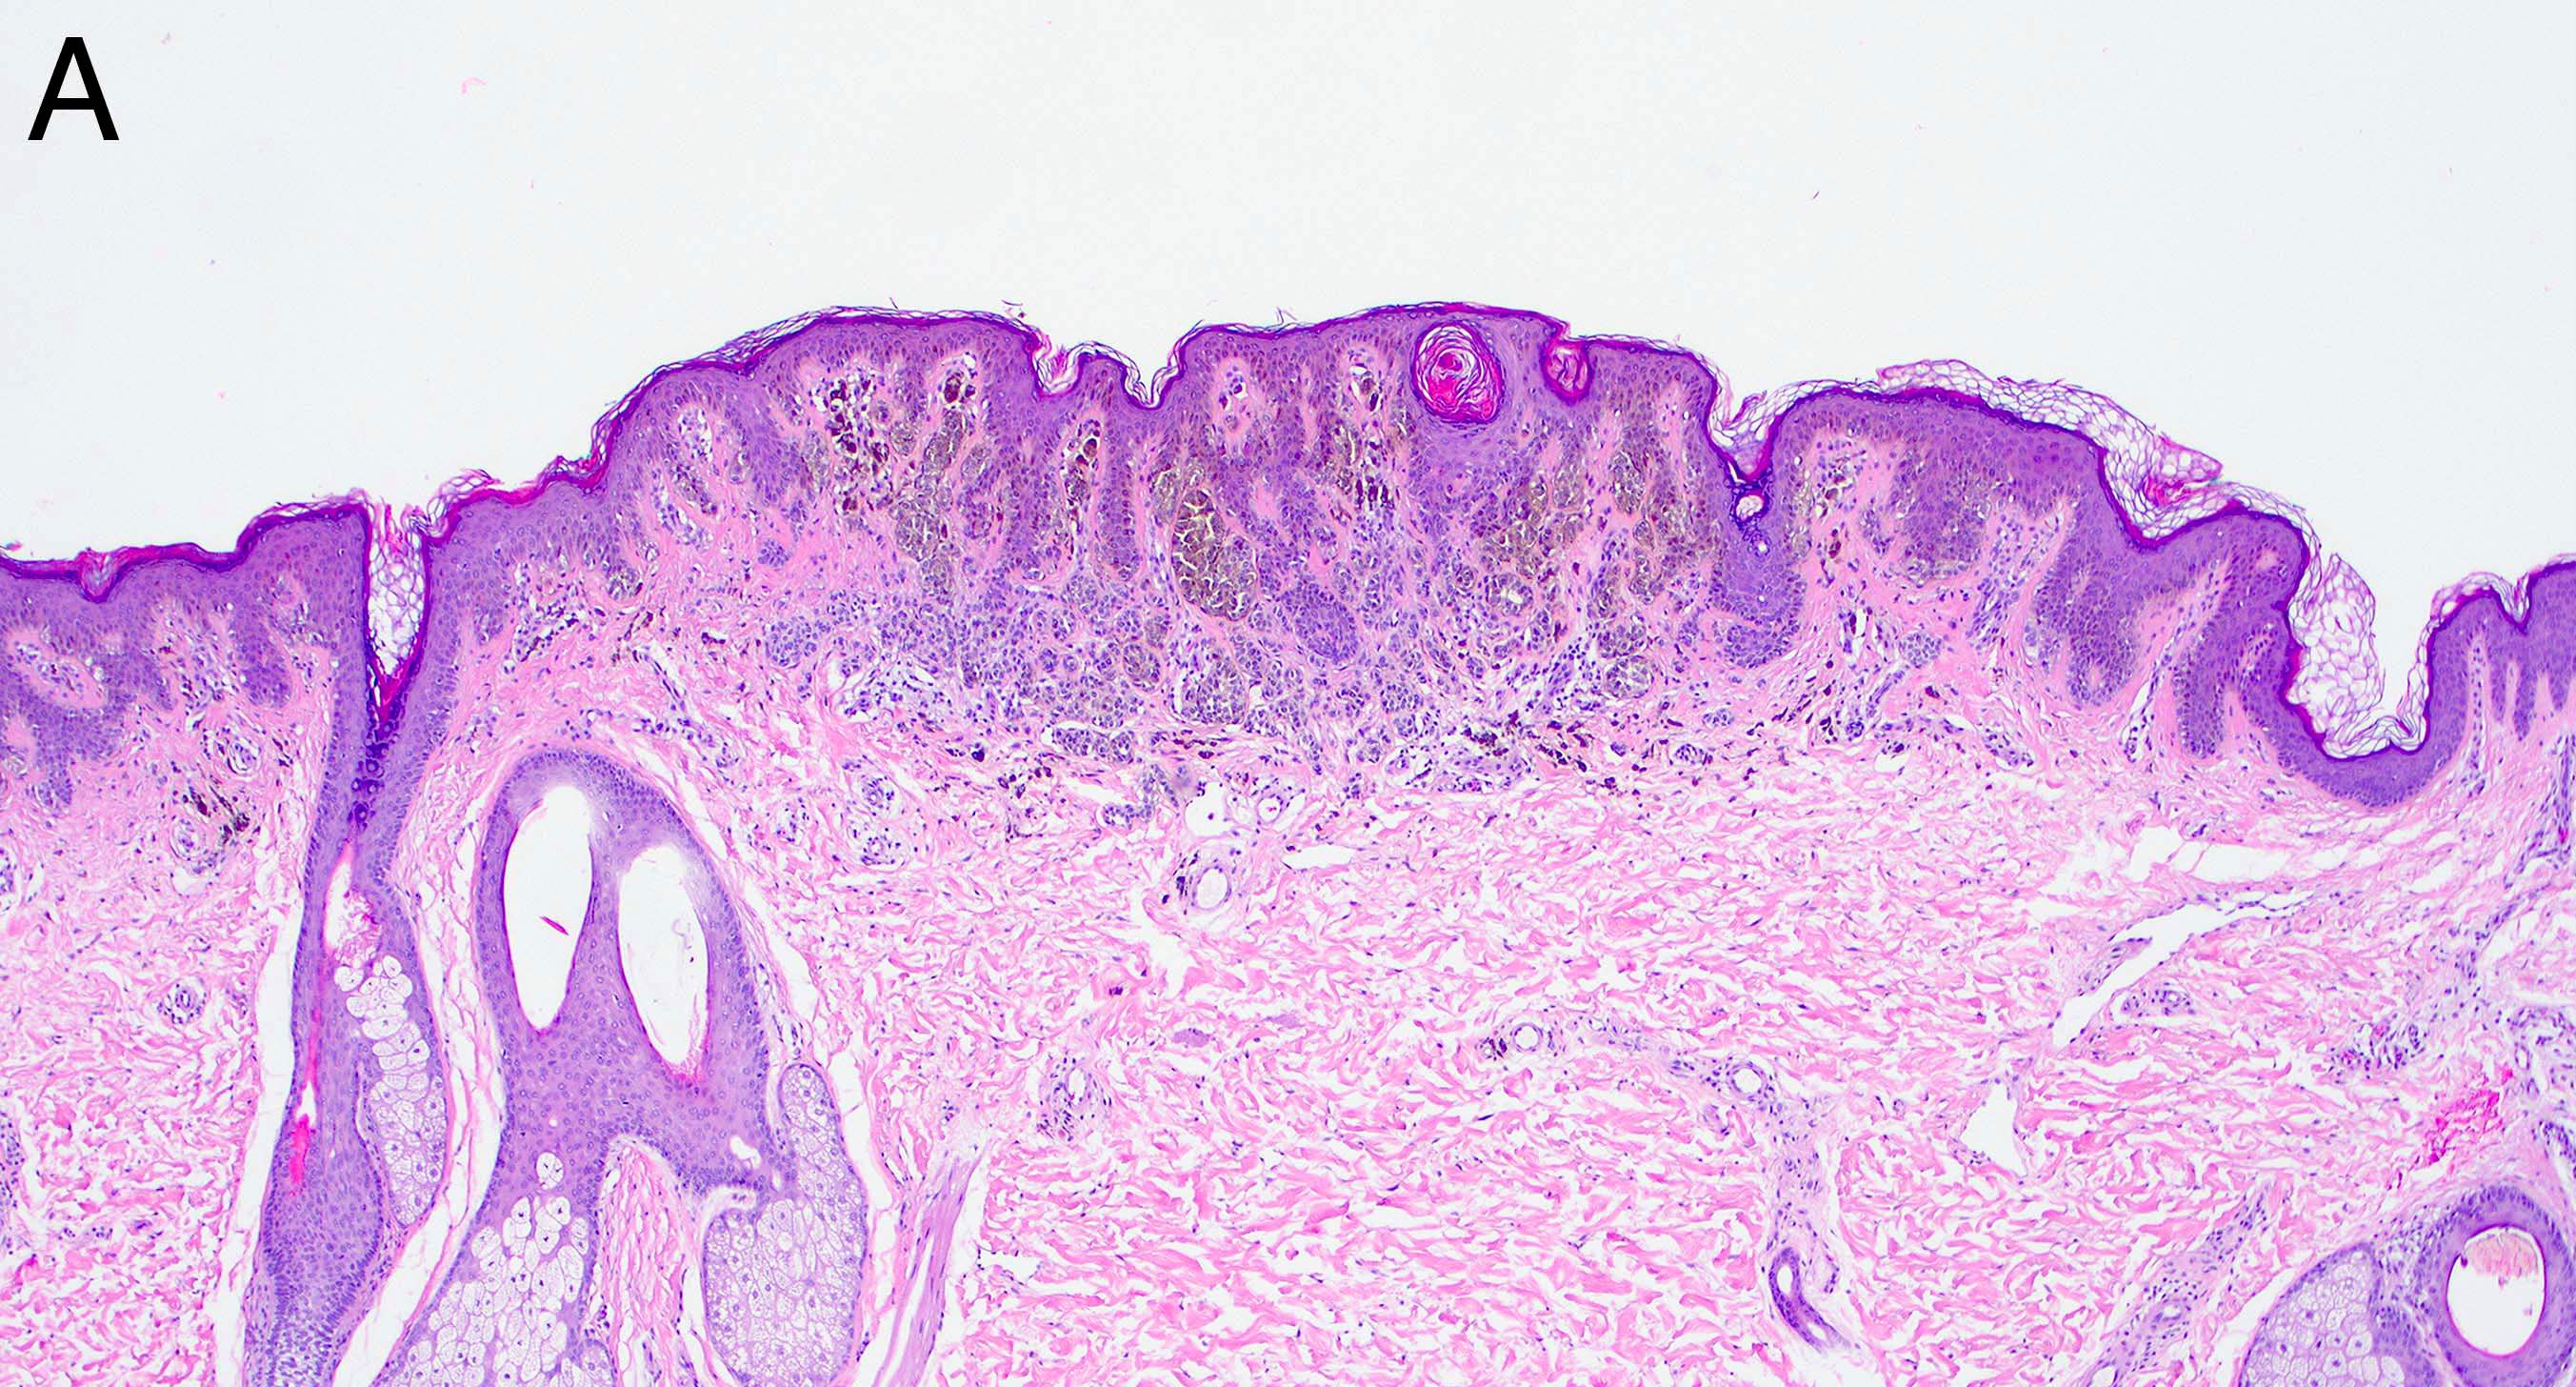

- Melanocytic nevi of the breast (Am J Dermatopathol 2016;38:867):

- May contain large irregular dyshesive nests in close proximity to one another

- Junctional nests may not be centered and can be placed within inter-rete spaces and along sides of rete

- Nests may have variable pigmentation (results in globules seen on dermoscopic exam)

- Nests may have prominent horizontal streaming resulting in rete blunting or epidermal effacement

- Cytologic atypia is common

- Maturation with melanocyte descent should be retained

Microscopic (histologic) images